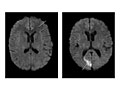

Abnormal:

Tumors in the brain or in areas outside the brain, such as an acoustic neuroma, are present.

Bleeding or swelling (edema) in or around the brain is present.

Areas of infection or inflammatory disease, such as encephalitis or meningitis, are present.

Abnormal areas in the brain may mean that certain diseases, such as Huntington's disease, multiple sclerosis, Parkinson's disease, or Alzheimer's disease, are present.

Bulges or weak areas (aneurysms) or abnormal blood vessels (such as an AV malformation) are present.

• Diffusion-perfusion imaging shows the water content and character of the brain. This method can give an early diagnosis of a stroke and may help predict the outcome of stroke. It can also be used to find tumors or inflammation of the brain.